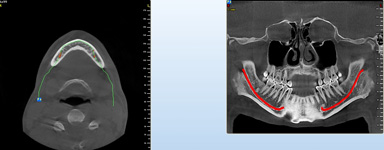

Pro následné plánování využíváme počítačové programy NewTom Implant Planning a coDiagnostiX, které slouží na plánování vhodných pozic pro zavedení implantátů, operačních šablon, kostních bloků, pozdějších protetických náhrad, ...

Plánování v implantologii musí být vždy zaměřeno na optimální výsledek, probíhá tedy obráceně „od konce do začátku“ ošetření – „backwards planning“. Znamená to, že po kompletním vyšetření pacienta, včetně CBCT scanu, zhotovíme pacientovi „model náhrady“ – tzv. Wax up, Set up,

Mock up, tedy jak by mělo definitivní ošetření vypadat. Na základě tohoto modelu pak pomocí plánovacích programů a všech získaných dat naplánujeme počet potřebných implantátů, jejich pozice, délky a průměry.

Mezi další počítačové programy, které máme dispozici, patří počítačový plánovací program

NewTom Implant Planning na plánování vhodných pozic pro zavedení implantátů. Dalším plánovacím softwarem, který umožňuje i zhotovení operačních šablon pro přesné zavádění implantátů - tzv. navigovaná implantologie, je software

coDiagnostiX od firmy Dental Wings (Německo).

Pomocí počítačových programů – NewTom Implant Planning a coDiagnostiX si lékař sám provádí veškerá potřebná zobrazení a měření.

Lékař si vytvoří všechny typy zobrazení potřebných pro naplánování – tedy 2D snímky (panoramatický), příčné řezy i 3D model.